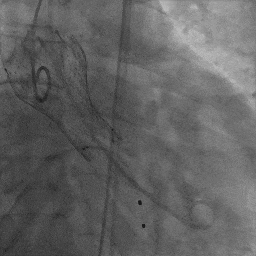

患者取平卧位,局麻镇静,颈内静脉置入中心静脉置管,测中心静脉压3cmH2O,左侧桡动脉穿刺置管监测动脉压力。术区无菌消毒铺巾,穿刺右侧桡动脉并置入6F鞘管,超声引导下穿刺双侧股动静脉,右股动脉预置两把Proglide缝合器,左侧股动静脉留置6F鞘管。将Lunderquist加硬导丝送至升主动脉,沿加硬导丝送20F GORE动脉鞘管。将临时起搏漂浮电极经右股静脉送至右室心尖部位,测试起搏器工作良好。予肝素6000单位,ACT大于250s。经左股动脉置入6F猪尾导管,在释放体位下行主动脉根部造影。经右侧桡动脉送脑保护装置分别在左颈总动脉、头臂干动脉释放保护。经右侧股动脉送入6F JL4.0造影导管造影提示:左前降支未见明显狭窄,TIMI血流III级;回旋支未见明显狭窄,TIMI血流III级。送入6F JR4.0造影导管造影提示:右侧冠脉未见明显狭窄,TIMI血流III级。在AL2导管指引下,直头导丝跨瓣至左心室,沿导丝送猪尾导管至左心室,测得跨瓣压差50mmHg。经猪尾导管送入塑形后的加硬导丝送至左心室内,沿加硬导丝送启明L26主动脉瓣系统至主动脉瓣处,在释放体位下释放至工作状态,经猪尾导管行主动脉造影示瓣膜定位良好。继续完全缓慢释放瓣膜。送入20×40mm球囊至主动脉瓣,在180次/分起搏下,收缩压下降至50mmHg时行球囊扩张,扩张无明显腰征。主动脉造影示瓣膜支架膨胀良好,微量瓣周漏。撤出输送系统。经胸超声评估主动脉瓣位为人工瓣回声,位置固定,瓣叶活动良好。主动脉造影提示主动脉无夹层、出血。行造影提示腹主动脉、髂动脉、股总动脉未见明显异常,缓慢撤出20F大鞘管,缝合右侧股动脉穿刺点,保留右侧临时起搏器并固定良好。

主动脉根部造影